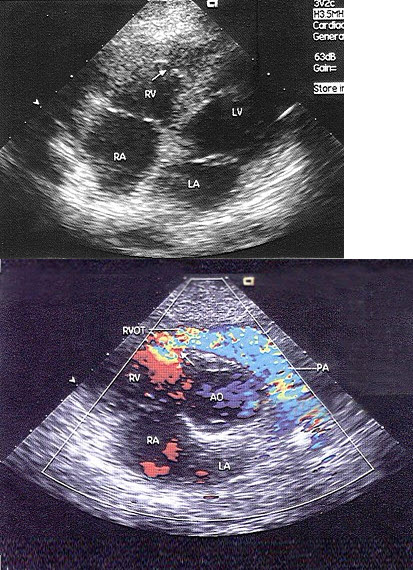

A.左心局部舒张功能

男28岁,胸部疼痛1周余,神清,心律齐,超声心动图如下,根据图片应提示()

A.单心室

B.心内膜垫缺损

C.三尖瓣上移

D.三尖瓣下移

E.三尖瓣狭窄